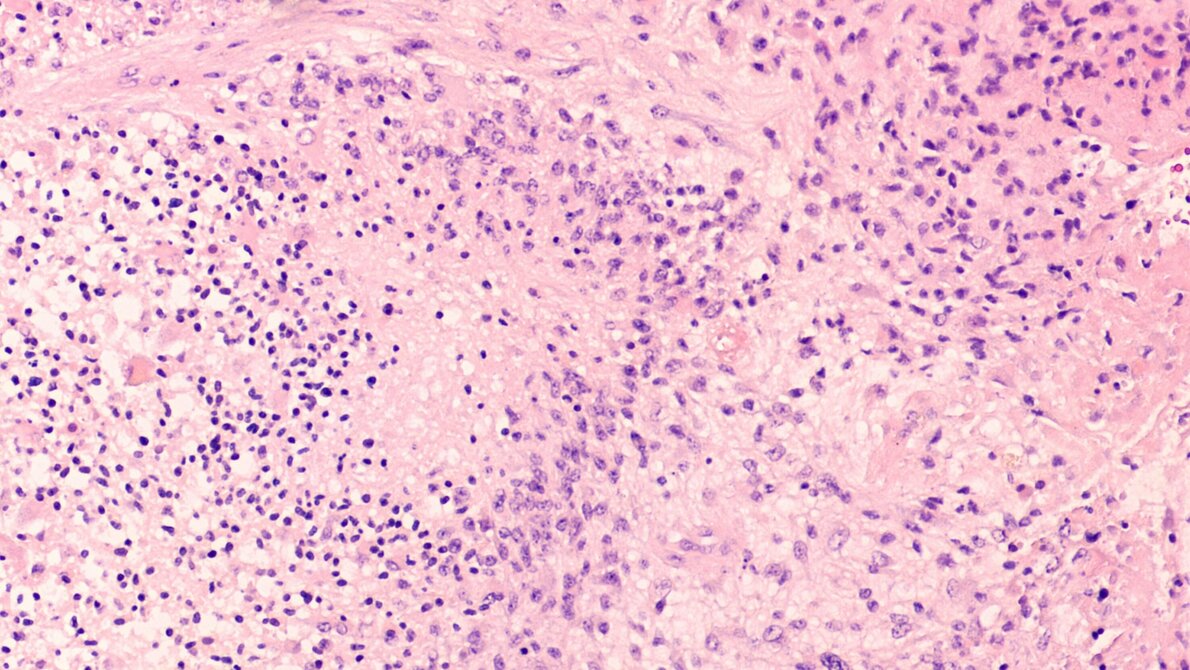

Allerdings sind seit vielen Jahren in der Wissenschaft Studien bekannt, wonach bestimmte Zellen des Gehirns körpereigene Cannabinoide ausschütten - die auch zur Selbstverteidigung gegen Glioblastome dienen. Das Glioblastom ist der häufigste und zugleich bösartigste Hirntumor, an dem allein in Deutschland jährlich etwa 4.000 Menschen erkranken. Etwa die Hälfte der Patienten überlebt vom Zeitpunkt der Diagnose gerechnet durchschnittlich nur 16 Monate. Neue Behandlungsformen sind deshalb dringend nötig.

In diesem Wissen und motiviert von den vorangegangenen Studien, haben die Forscher/-innen nun den Effekt von CBD gegen Tumorzellen aus Mäusen und Menschen getestet. Die Zellen wiesen etliche Mutationen auf, die für Glioblastome typisch sind. Resultat: Binnen zwei bis drei Tagen nach Gabe des Cannabidiols sterben diese Glioblastomzellen ab. „CBD induziert den Zelltod bestimmter Glioblastome, es gibt aber auch Tumore, die nicht therapeutisch auf CBD ansprechen“, sagt Glaß. Außerdem haben die Forscher/-innen ermittelt, „dass CBD einen Signalweg blockiert, der ansonsten Entzündungsreaktionen kontrolliert.“ Die Tumorzellen nutzen diesen Signalweg, um immer weiter zu wachsen. Glaß‘ Team hat zudem einen „Marker“ gefunden, der anzeigt, welche Glioblastome höchstwahrscheinlich auf CBD ansprechen werden und welche nicht.